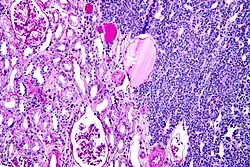

Micrograph of a metanephric adenoma with structures reminiscent of those seen in papillary renal cell carcinoma. H&E stain.

Metanephric adenoma (MA) is a rare, benign tumour of the kidney, that can have a microscopic appearance similar to a nephroblastoma (Wilms tumours),[1] or a papillary renal cell carcinoma.

Metanephric adenoma is diagnosed histologically. The tumours can be located at upper pole, lower pole and mid-hilar region of the kidney; they are well circumscribed but unencapsulated, tan pink, with possible cystic and hemorrhagic foci. They show a uniform architecture of closely packed acinar or tubular structures of mature and bland appearance with scanty interposed stroma.[3][4][5][6][7] Cells are small with dark staining nuclei and inconspicuous nucleoli. Blastema is absent whereas calcospherites may be present. Glomeruloid figures are a striking finding, reminiscent of early fetal metenephric tissue. The lumen of the acini may contain otherwise epithelial infoldings or fibrillary material but it is quite often empty. Mitoses are conspicuously absent.[3][4][5][6][7] In the series reported by Jones et al. tumour cells were reactive for Leu7 in 3 cases of 5, to vimentine in 4 of 6, to cytocheratin in 2 of 6, to epithelial membrane antigen in 1 of 6 cases and muscle specific antigen in 1 of 6.[5] Olgac et al. found that intense and diffuse immunoreactivity for alpha-methylacyl-CoA racemase (AMACR) is useful in differentiating renal cell carcinoma from MA but a panel including AMACR, CK7 and CD57 is better in this differential diagnosis.[8] Differential diagnosis may be quite difficult indeed as exemplified by the three malignancies initially diagnosed as MA that later metastasized, in the report by Pins et al.[9]